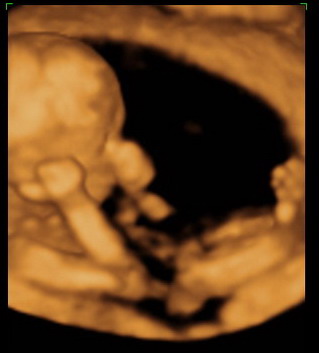

Gratula a kukishoz! Úgy tűnik minden Kisfiúnak ez a szokása! Apa akkor nagyon büszke :lol: :lol: ! Rajta múlt :D ! Kép KUKAC

Kép levitáció Kép Orr+fülfogás

Kép BOX

Kép Lúdtalp nincs :):)lábfej torna Kép Kép Álmos vagyok

Kép guggolás Kép Tipikus pasi-láb között matatás

Kép Nyújtózás

Kép Hello Kép Elég volt, most már alszom